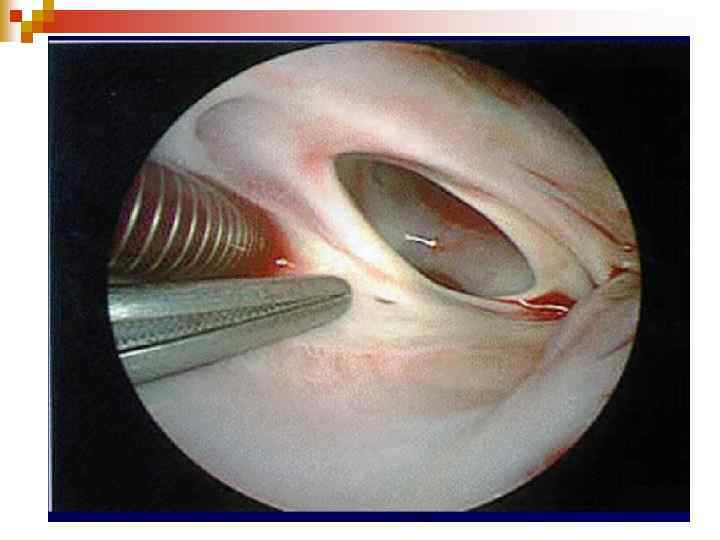

Cardiac catheterization lab

ДМПП